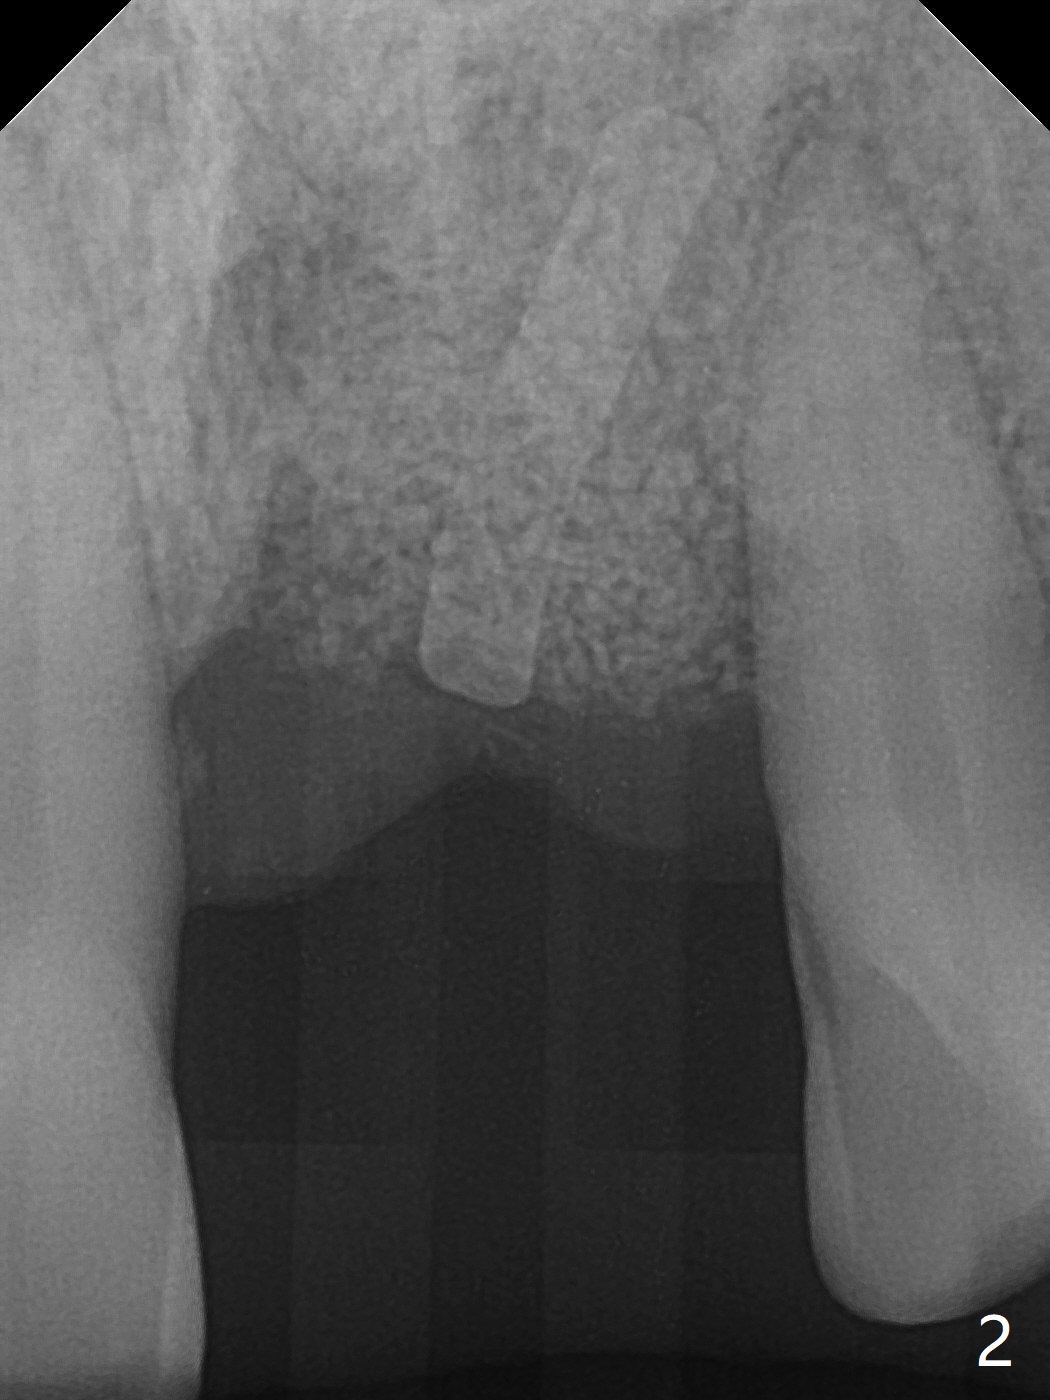

A 67-year-old man requests extraction of the loose tooth #9 (Fig.1). After extraction, the labial plate is found to be missing. With incision, allograft is kept in place with a 12x24 mm anterior narrow Cytoplast and 4-0 Chromic gut suture (Fig.2). Periodontal dressing dislodges in 2 days. The wound dehisces transversely 5 days postop (Fig.3 arrows), whereas the wound was open buccopalatal when the sutures were placed. Probably due to extensive dissection, the erythematous mucosa is large (Fig.4), although asymptomatic. When X-ray shows V-shaped bony defect (Fig.1 (PA), 5 (Pan), 6 (CT)), do not dissect the overlying thin buccal gingiva, which is most likely to dehisce. In fact immediate implant with guide appears to be more conservative, since there is no pressure against the buccal gingiva (Fig.7,8). To be more ideally, the implant could be placed more coronally, longer (13 mm instead of 11.5, Fig.9,10) and narrower (3.5 mm instead of 4.0 mm, Fig.11 (red circles: bone graft)).